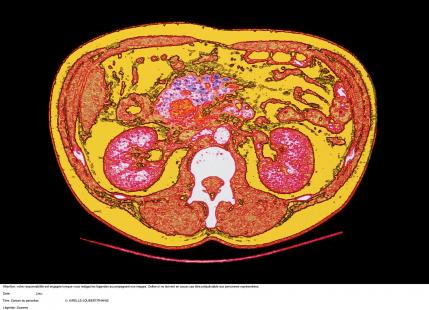

Crédit photo : PHANIE

DES MICROARN qui peuvent être détectés dans des échantillons sanguins pourraient permettre de dépister les patients porteurs d’un cancer du pancréas, selon les résultats de chercheurs de l’université du Texas (Houston).